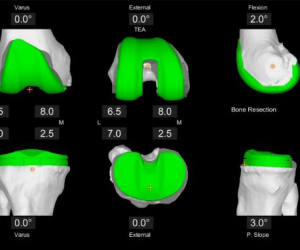

First, a CT scan of the diseased knee joint is taken. This CT scan is uploaded into the Mako System software, where a 3D model of your knee is created. This 3D model is used to pre-plan and assist your surgeon in performing your total knee replacement.

Patient-specific pre-operative plan enables more accurate implant positioning. CT data is segmented to create a 3D model of the patient’s bone anatomy. An individualized pre-operative plan is created and reviewed with you prior to the Mako procedure.

Mako_Total_Knee_3D_planning

Surgeon-controlled intra-operative adjustments can be made to optimize implant placement. Kinematic and soft tissue data are collected intra-operatively and applied to the virtual CT model.

You can review the pre-op plan and can modify it if necessary based on the intra-operative data to virtually balance the joint and achieve individualized placement.